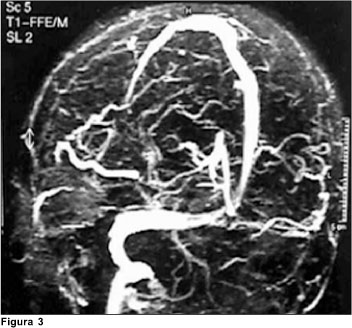

Dos exames de imagem, foram solicitados: tomografia de crânio, que evidenciou assimetria ventricular, às custas de diminuição de ventrículo lateral à direita e tomografia de órbita (Figura 1), que revelou ingurgitamento de veia oftálmica à esquerda. A ressonância de crânio demonstrou redução do fluxo em seio cavernoso à esquerda (Figura 2). A angiores-sonância de crânio demonstrou: redução acentuada do fluxo venoso através do seio transverso esquerdo, sigmóide, seio cavernoso e veia jugular homolateral, correspondendo a trombose nestes segmentos; veias tributárias de convergência apresentavam-se túrgidas e proeminentes (Figura 3).

O diagnóstico de trombose do seio cavernoso é eminentemente clínico e seu prognóstico é diretamente influenciado pelo tratamento precoce adequado(9). Após a suspeita clínica, solicitamos exames de imagem para confirmação diagnóstica, sendo o exame de escolha a ressonância nuclear magnética (RNM), seguida da angiorressonância de crânio(1).